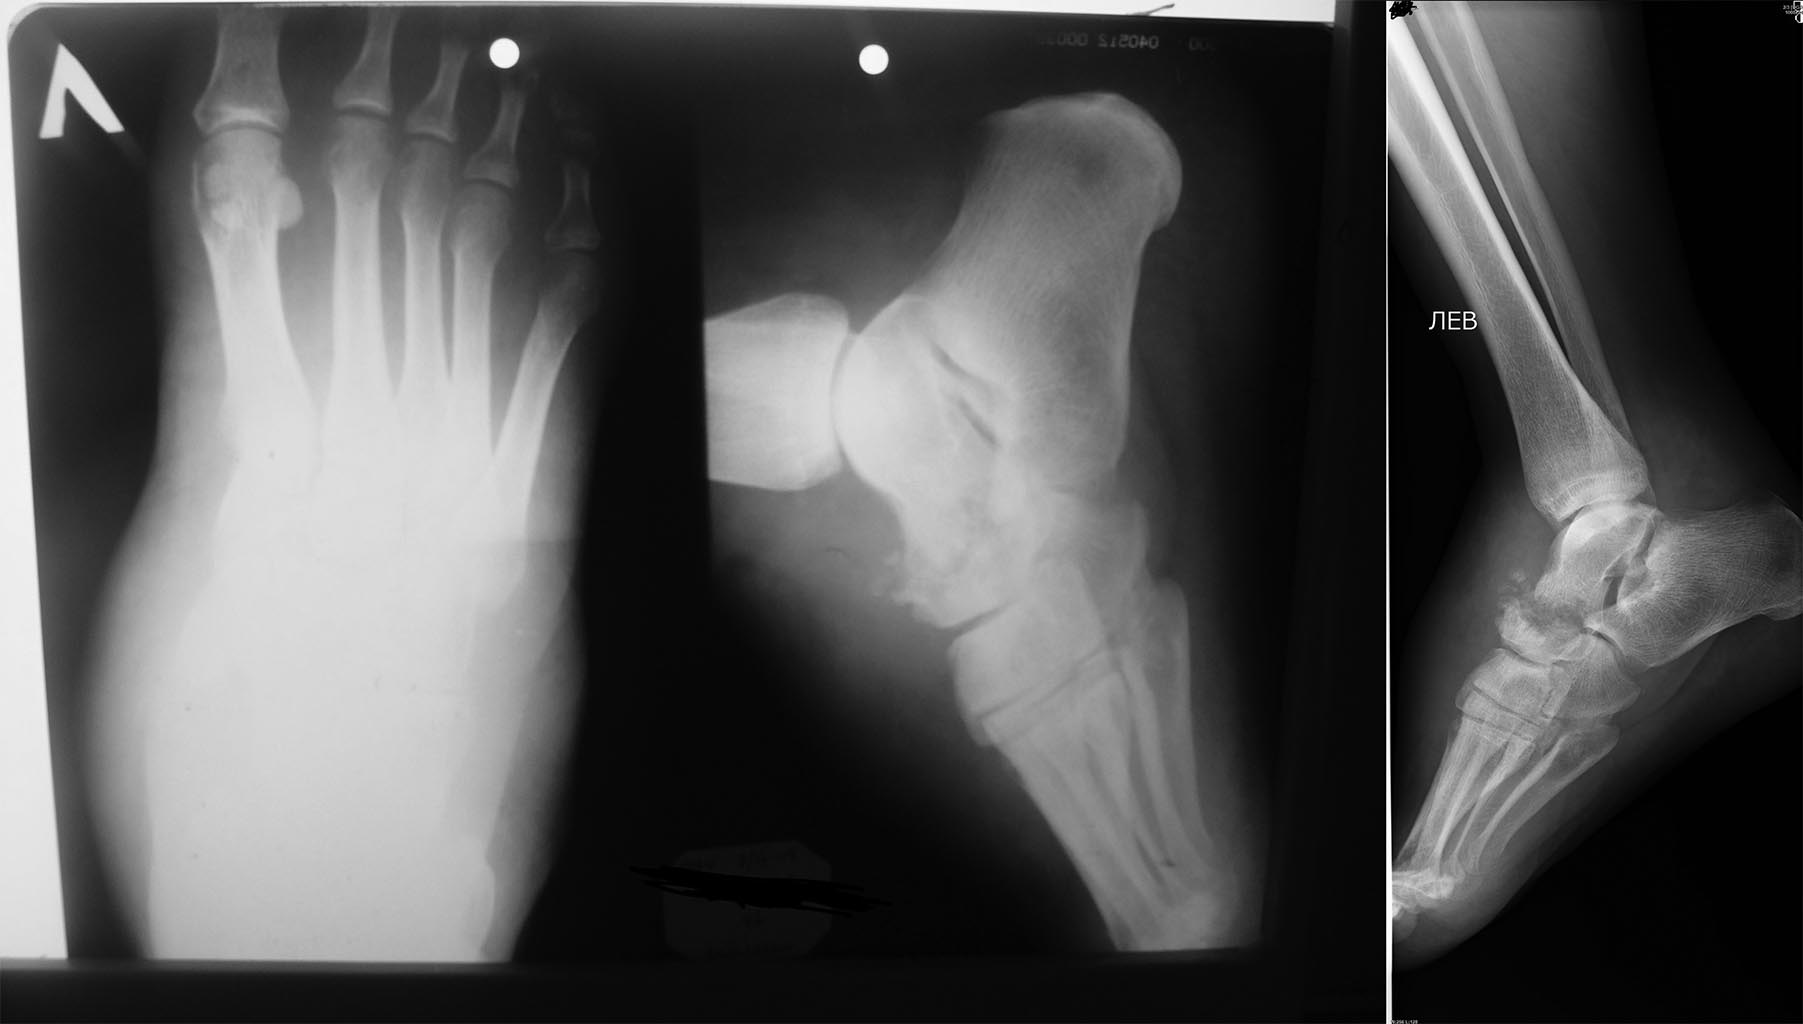

Новообразование стопы

Пациент с жалобами на боль в стопе, усиливающуюся при ходьбе, объемное образование тыла стопы 6,0*6,0 см. Болеет около 1 года. Осмотрен онкологом онкодиспансера - без онкопатологии ( по результатам биопсии). Консультация тубостеолога - ТБС не обн. При исследовании обнаружили новообразование дистального метаэпифиза большеберцовой кости и бедренной кости. Помогите пожалуйста определиться с диагнозом и методом лечения.

А все-таки что в биопсии? Каким способом она выполнялась? Нет онкологии, но что-то же есть? Сколько лет пациенту? Страдает ли сахарным диабетом? Есть ли симптомы периферической нейропатии? Ведь при такой деструкции не очень-то походишь, если только не нарушена чувствительность. Что за объемное образование: плотное, болезненное, подвижное? Может быть стоит прислать фото стопы и КТ бедренной кости? И томограммы стопы разбить на несколько частей, уж больно маленькие.

Биопсия выполнялась дважды в онкодиспансере (как не знаю), в условиях отделения - троакаром. Результат: клетки крови с преобладанием лимфоцитов, единичные фиброциты, некротические массы, немного межуточного оксифильного вещества. Элементов злокачественного новообразования не обнаружено. Пациенту 50 лет. Из сопутствующей патологии гипотиреоз, анемия неясного генеза. СД нет. Новообразование умеренно плотное, не спаяно с кожей, не подвижное, безболезненное при пальпации. КТ бедренной кости нет. Рг-коленного сустава и детальноМРТ выложу чуть позже. Может быть есть какие-нибудь предположения?.

Вполне может быть диффузная B-крупноклеточная лимфома например, тем более есть анемия, направьте пациента в РОНЦ Блохина, там занимаются костными опухолями плотно, в любом случае без постановки диагноза какие либо операции делать нельзя!!